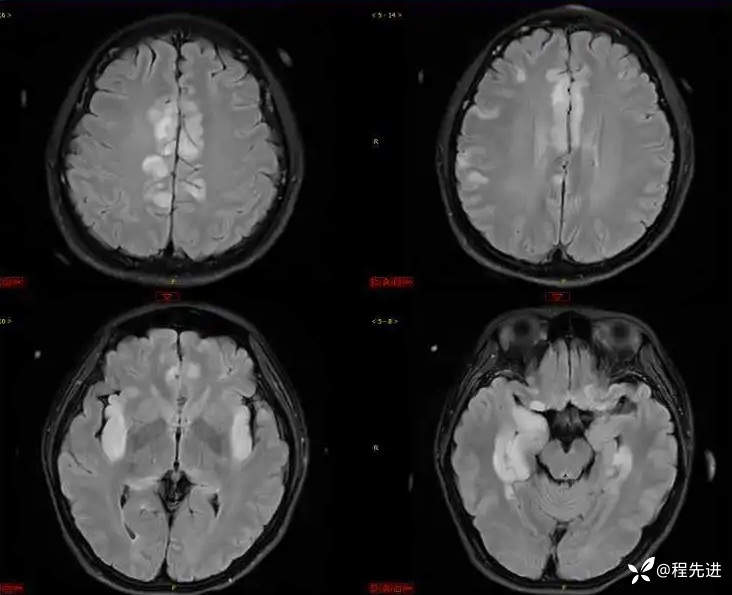

FLAIR: